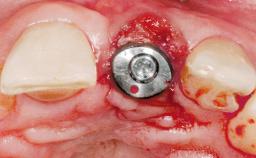

Type of Implants Two-Piece

Attachment Two-Piece

Abutment Type Customized

Placement Protocol Early or late implant placement

Bone Volume Deficient horizontally, requiring prior grafting